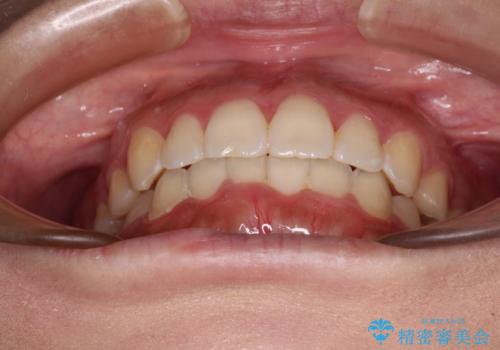

前歯のデコボコをインビザラインでスッキリと

日々の装着時間をしっかりと守って治療の臨んでくださったため、治療前のシミュレーションに近い形で矯正治療を進めて行くことができました。